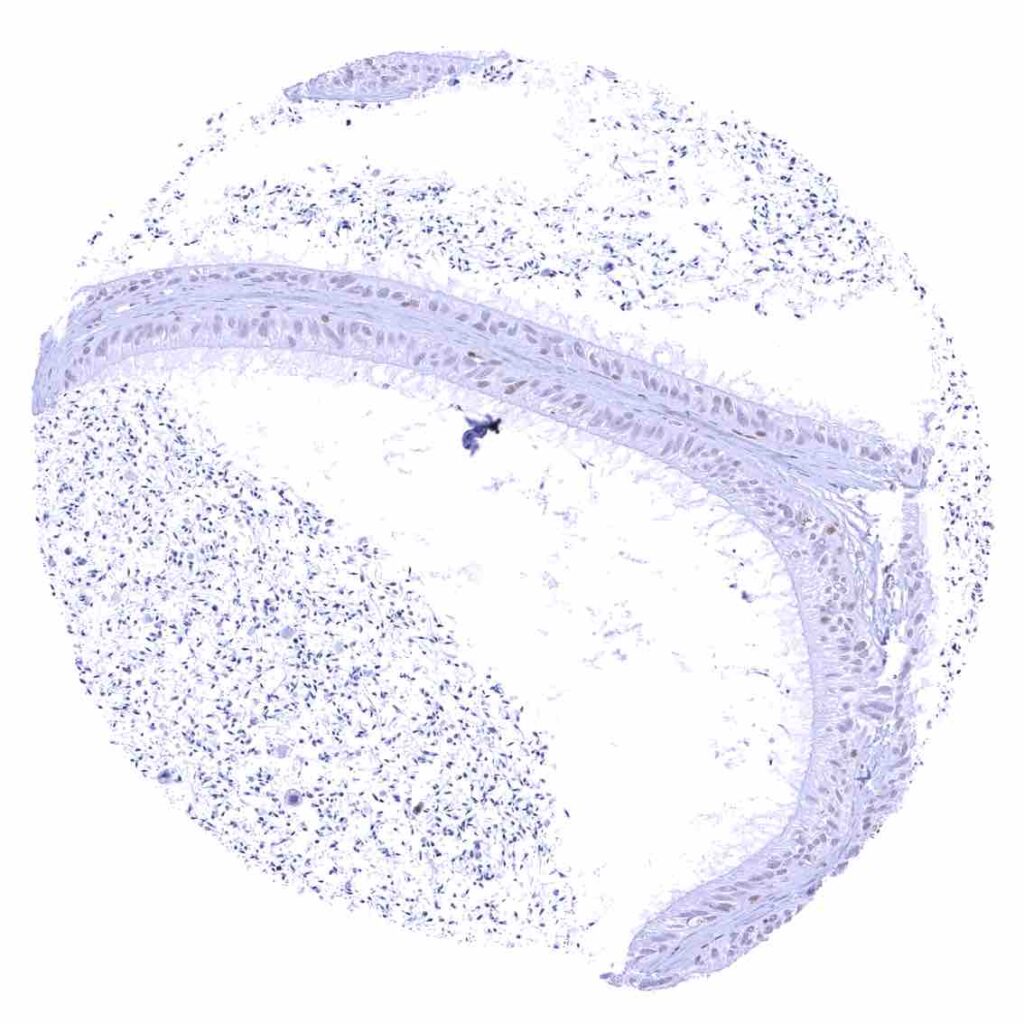

Urinary bladder, urothelium